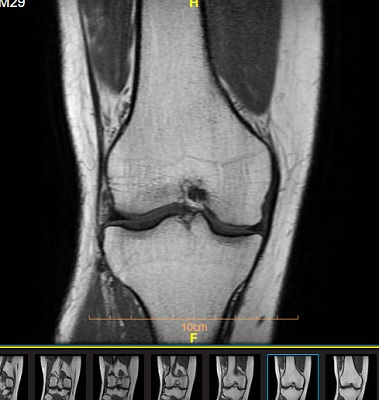

• تصویر برداری پزشکی : تصویر برداری نقش مهمی در تشخیص و پیگیری آرتریت روماتوئید دارد :

3. ام آر آی : شناسایی تغییرات اولیه مفصل قبل از بروز آسیب های واضح استخوانی

نکته : ام آر آی و سونوگرافی می توانند بیماری آرتریت روماتوئید را در مراحل ابتدایی ، حتی قبل از تخریب مفصل شناسایی کنند.